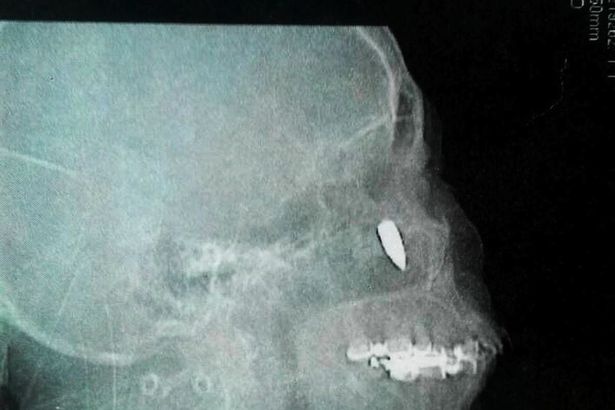

Rang moc trong hoc mui hinh anh

Răng mọc trong hốc mũi

0

Các bác sĩ phẫu thuật và lấy chiếc răng dài 1 cm mọc bất thường trong mũi một người đàn ông Ả Rập.